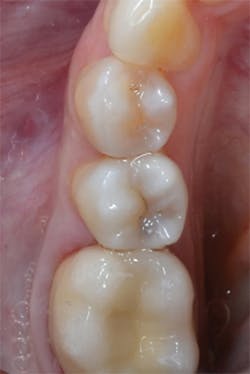

Figure 14: Final restorations on teeth Nos. 4 and 5.